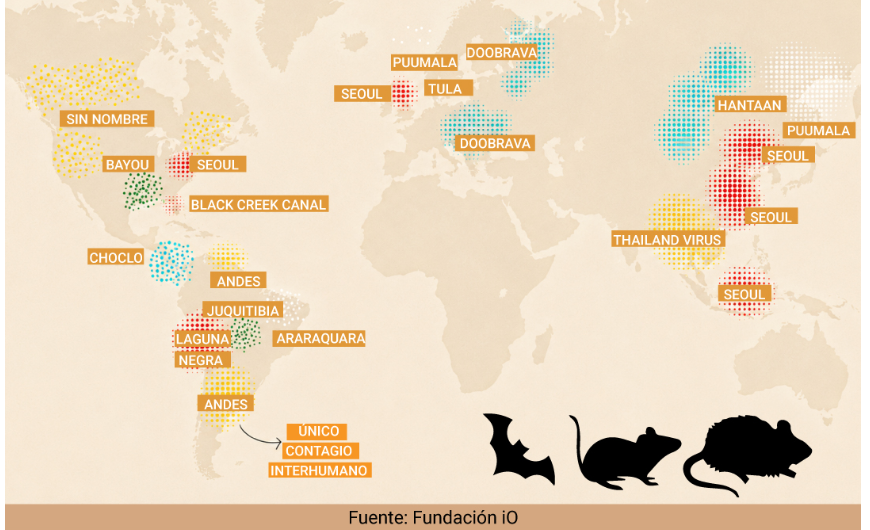

Mapa mundial del hantavirus: hay una gran variedad de cepas en regiones muy diferentes con un factor común

Las autoridades sanitarias internacionales han realizado operativos coordinados tras la confirmación de un brote mortal en un crucero que quedó varado en Cabo Verde Un brote mortal de hantavirus a bordo del crucero holandés MV Hondius, que permanece frente a las costas de Cabo Verde con cerca de 150 personas, encendió alertas sanitarias internacionales tras la detección de una cepa con […]